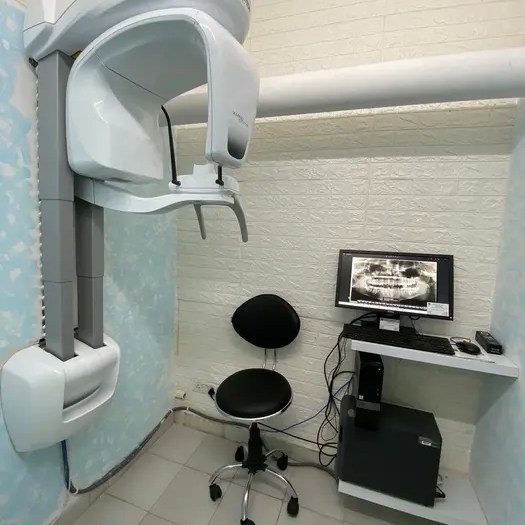

The picture gallery at Gracious Smiles showcases some of the remarkable transformations our patients have achieved through the range of dental treatments. From before-and-after photos of dental implants, Invisalign aligners, and braces to images of successful TMJ treatments, the gallery provides a visual representation of the high-quality care that patients can expect at Gracious Smiles. The photos are a testament to the expertise and dedication of our dental professionals in helping patients achieve their dream smiles.